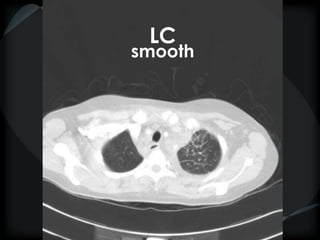

Septal Pattern – lymphatic/venous

● Smooth – pulmonary veno-occlusive disease, mitral

stenosis, capillary hemangiomatosis, LC

smooth

LC